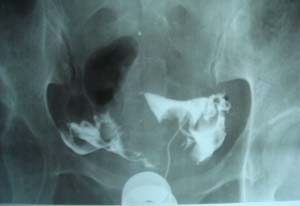

双侧输卵管是通的。

子宫输卵管造影未见明确异常。

子宫腔光整,双侧输卵管通畅,盆腔内造影剂弥散可。

各位子宫内是有个圆形充盈缺损,子宫呈倒“三角形”形态没有完全被造影剂充盈呀。子宫肌瘤。应该在拍两张斜位就好了 。

子宫体确有充盈缺损。考虑子宫肌瘤。子宫左倾

子宫输卵管造影未见明显异常,宫内充盈负影为气囊压迫所致。